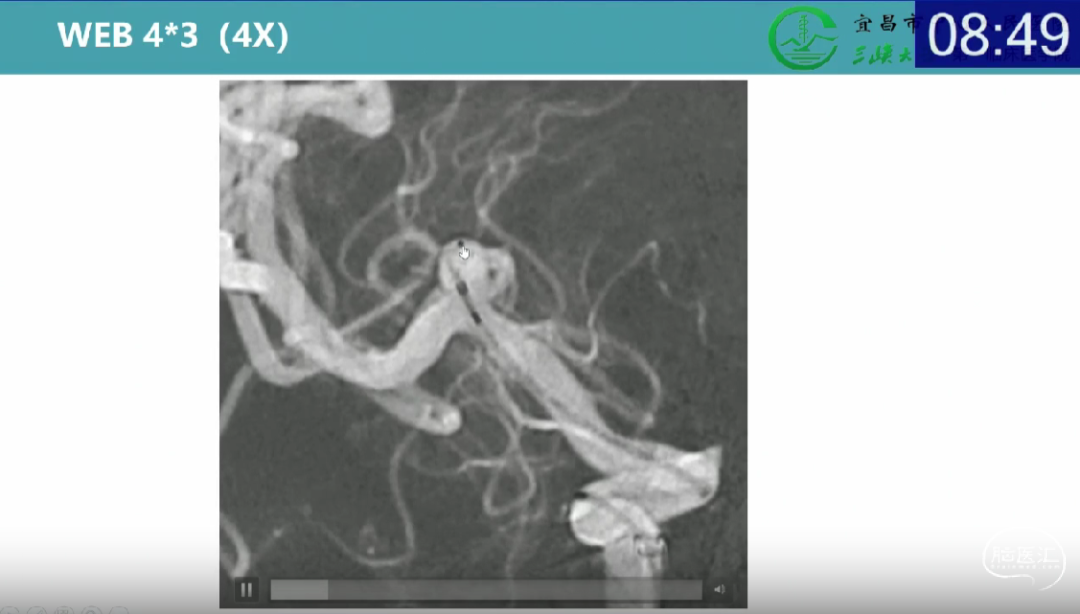

·两个正交位的平均瘤体宽度

·两个正交位的瘤颈宽度

·两个正交位的最小高度

·测量多角度投影尺寸,通过2D或3D影像测量,形态越不规则对测量要求越高。

·动脉瘤瘤体成角或有子瘤、小泡时测量要排除在外。

·使用预期的WEB放置位置进行动脉瘤高度测量,而不是从瘤颈到瘤顶最高点的高度。